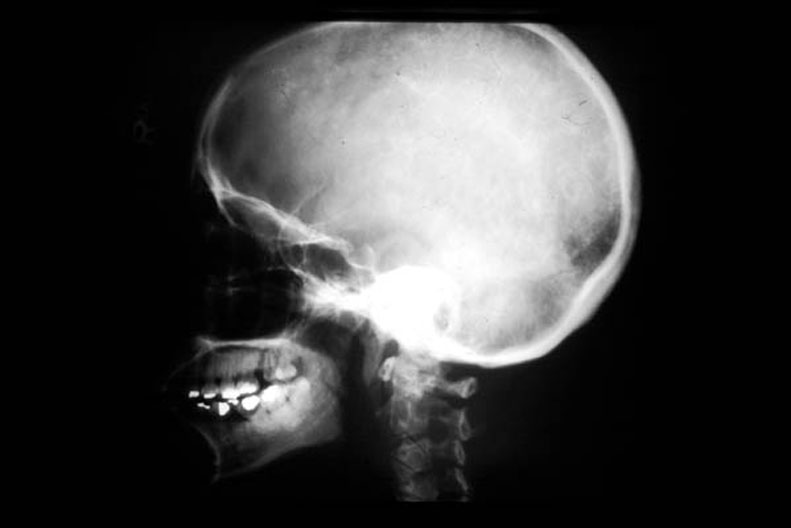

Lateral X-Ray of the Skull

Roll mouse over image to display labels.

1. Hypophyseal fossa

2. Axis

3. Odontoid process

4. External occipital protuberance

5. Temporal bone